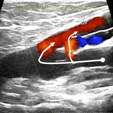

Corso di introduzione alla diagnostica emodinamica ecocolordoppler della IVC